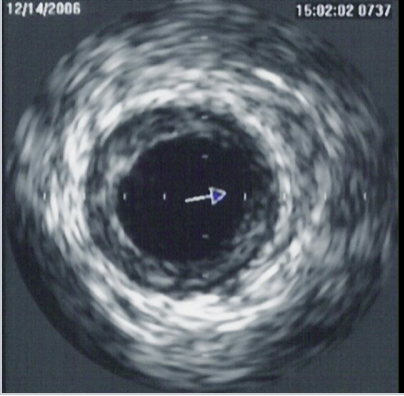

Intra-Coronary Imaging

Sometimes an X-ray alone doesn’t give enough detail. Intra-coronary imaging allows us to look inside the artery from within. This helps to gain an understanding how severe a narrowing really is, choosing the right size and length of a stent and ensuring the stent is perfectly positioned and expanded

There are two main techniques; ultrasound inside the artery – shows vessel size and plaque build-up and light-based imaging – provides very high-resolution detail. These techniques help tailor treatment to your individual anatomy, improving safety and long-term outcomes.